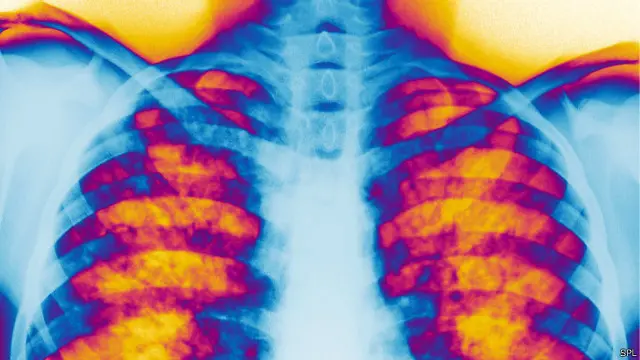

وغالبا ما يموت المرضى المصابون بالتليف قبل الأربعينيات لأن المخاط يؤدي إلى انسداد الرئتين والإضرار بهما، ما يجعل المرضى عرضة للإصابة بالعدوى.

وتؤدي العيوب في الحمض النووي (DNA)، التي يرثها المرضى من آبائهم، إلى الإضرار بقدرة الجسم على التحكم في مستويات الملح والماء في بطانة الرئتين.

وفي هذه الحالة تكون النتيجة هي تكون طبقة من المخاط السميك التي تضر الرئتين.